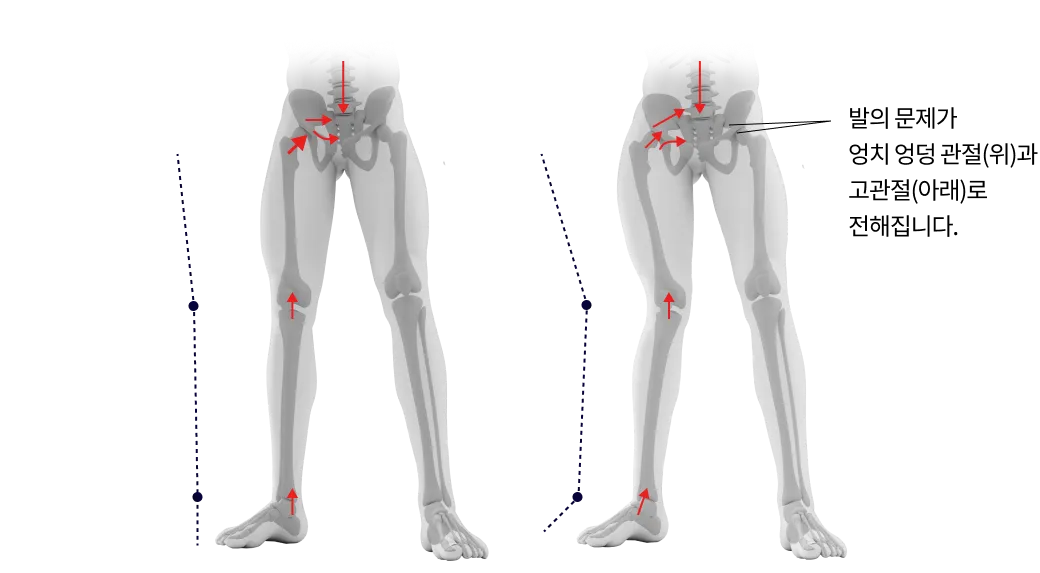

발의 문제는 전신통증의 시작입니다.

발은 우리 몸에서 건물의 주춧돌과 같은 역할을 합니다. 발의 틀어짐으로 인한 통증은 단순히 발의 문제로 그치지 않고 보행 패턴을 무너뜨리며 다리와 무릎 관절, 나아가 골반과 허리의 추간판까지 연쇄적인 영향을 미칩니다. 발의 문제를 조기에 발견해 치료하는 것이 전신 건강을 위해 중요합니다.

척추와 골반이 틀어지면 체중이 고르게 분산되지 않고 보행 패턴도 불균형해져서 한쪽 발에 과도한 부담이 집중됩니다. 여기에 척추 디스크나 협착증으로 인한 신경 압박은 발의 통증을 더욱 악화시키는데, 특히 노화로 엉덩이 근육이 약해지면서 통증이 가속화 되는 경우가 많습니다. 발 질환의 효과적인 치료를 위해서는 척추와 골반을 바로 잡아 양발에 체중이 균등하게 분산되도록 하는것이 중요합니다.

무릎의 변형을 발질환에 많은 영향을 미칩니다.

O 다리나 X 다리 , 무릎이 뒤로 밀려난 슬관절과신전 패턴 등은 보행패턴을 망가뜨리고 정상적인 보행을 방해하여 발질환을 만성화시키는 주 원인이 됩니다.